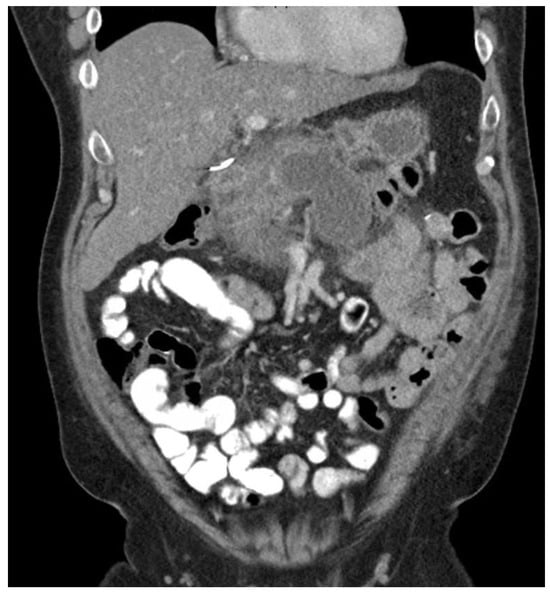

3.2. Severity of Pancreatitis

The prediction of severity is made upon the admission of the patient, but the actual degree of severity is determined once sufficient time has elapsed in order to make a better assessment of acute pancreatitis. The most widely accepted classification of severity is the Revised Atlanta Classification (RAC) [4], which classifies pancreatitis as follows: (1) mild acute pancreatitis with no local inflammation or organ failure, (2) moderately severe acute pancreatitis with transient organ failure (<48 h) or local complications, and (3) severe acute pancreatitis with persistent organ failure (>48 h). In total, 65–70% of patients with acute pancreatitis have an uncomplicated course in which the symptoms resolve within a few days [4,43]. A total of 20–25% of patients develop moderate acute pancreatitis with local pancreatic injury fluid collection or necrosis, leading to prolonged hospitalization. This progression is displayed in Figure 4, Figure 5 and Figure 6. About 10% of patients develop severe acute pancreatitis accompanied by severe pain, a nutritional deficit, and a hospital stay > 4 weeks. These patients require highly intensive critical care with interventions (as indicated) [24].

Figure 4. Pancreatitis with CT showing walled-off necrosis.